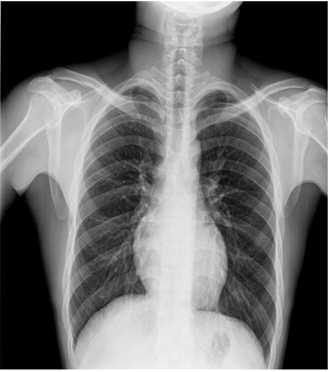

臨床圖片

微信圖片_20210927001116